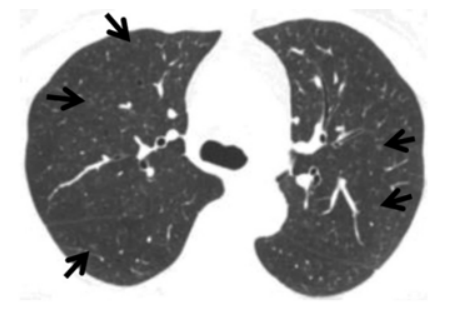

患者,男性,69岁,退休。2022年11月8日入院。主诉:体检发现左肺下叶结节半月余。既往史:既往体健,高血压病。胸部CT:左肺下叶磨玻璃影,两下肺间质性改变(图1),考虑感染?营养不良-炎症-动脉粥样硬化(MIA)?入院诊断为:左肺下叶结节:肿瘤?高血压病。

患者于2022年11月10日在全身麻醉下行左肺下叶部分切除+淋巴结活检术,手术过程顺利,入量1200 ml,尿量600 ml,出血10 ml。术后病理提示微浸润腺癌。术后顺利拔除气管插管,生命体征平稳。术后第3天开始出现活动后稍气喘,无明显发热,偶有咳嗽,咳白色黏痰。胸闷气喘症状逐渐加重。肝肾功能正常,D-二聚体正常,心肌标志物正常,未查血气和胸部CT;白细胞、CRP升高明显(表1)。予哌拉西林他唑巴坦+莫西沙星加强抗感染治疗。术后第5天胸部CT可见少量病灶(图2)。术后第12天胸部CT提示两肺间质性改变,右肺为著,局部可见支气管牵拉变形,磨玻璃影(图3)【普通感染不应出现如此变化,但当时并未引起重视】。后续患者出现呼吸衰竭,血气分析:pH 7.34,PaO2 53.1 mmHg,PaCO2 35.1 mmHg(面罩吸氧10 L/min)。转至ICU进一步治疗。